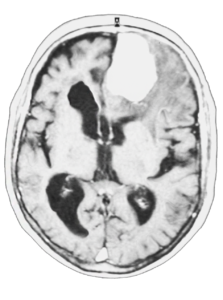

Los implantes son modelados y diseñados utilizando las imágenes obtenidas de una tomografía computarizada (Ctscan) o a partir de una resonancia magnética (MRI).